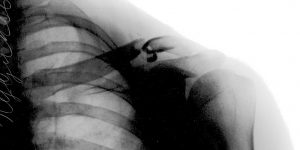

Перелом ключицы — распространенная и довольно неприятная травма. При смещении отломков часто требуется операция и длительная реабилитация.